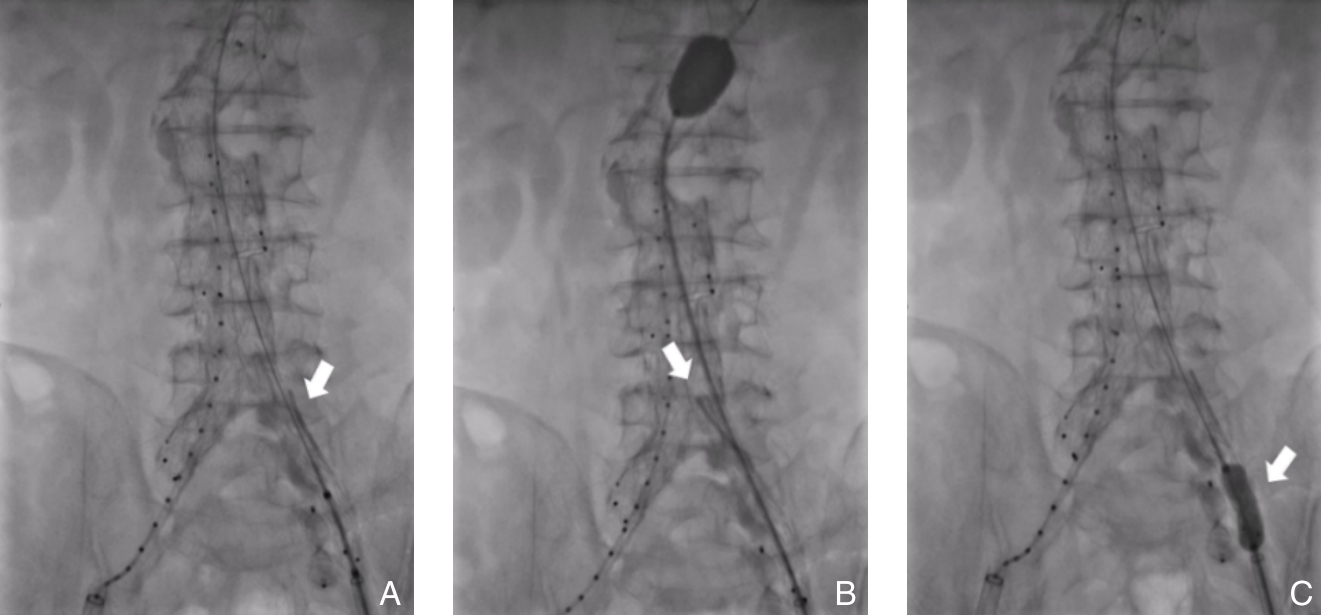

• Clinical application of three-dimensional visualization technology in assessing the spatial configuration of major hepatic vessels and liver lobar volume distribution

2026, 35(1):124-140. DOI: 10.7659/j.issn.1005-6947.250635

Abstract (93) HTML (137) PDF 3.82 M (171) Comment (0) Favorites

Abstract:Background and Aims The hepatic vascular and biliary systems exhibit substantial anatomical variability and complex spatial relationships, posing challenges for precise surgical planning based on conventional two-dimensional imaging. This study aimed to evaluate the clinical value of three-dimensional visualization in characterizing the spatial architecture of hepatic vasculature and bile ducts and to explore its association with hepatic volumetric distribution.Methods A total of 610 living liver donors and 158 patients with bile duct dilatation were retrospectively analyzed. Three-dimensional models of the hepatic artery, portal vein, hepatic veins, and bile ducts were reconstructed from contrast-enhanced CT images. Vascular and biliary anatomical patterns, spatial relationships, and their correlations with hepatic lobe and segmental volumes were systematically assessed.Results Three-dimensional visualization enabled intuitive and comprehensive depiction of hepatic vascular and biliary anatomy. Distinct portal vein configurations were associated with significant differences in regional liver volume distribution, with an increased proportion of the right posterior lobe observed in patients with specific portal vein branching patterns. The presence of an inferior right hepatic vein with a diameter ≥5 mm was also associated with a larger right posterior lobe volume. Analyses of extrahepatic and intrahepatic spatial relationships revealed relatively consistent positional patterns between the right hepatic artery, portal vein, and bile ducts, and a significant correlation was observed between the spatial courses of the right hepatic artery and the right posterior bile duct.Conclusion Three-dimensional visualization provides accurate preoperative assessment of hepatic vascular and biliary anatomy and clarifies complex spatial relationships and their volumetric implications. This technique offers critical anatomical support for precision hepatobiliary surgery and liver transplantation.